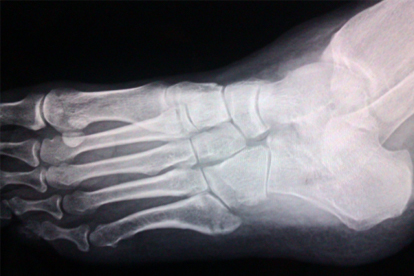

脚骨裂可通过制动固定、冷热敷交替、药物治疗、营养支持和康复训练等方式恢复。脚骨裂通常由外伤、骨质疏松、重复应力等因素引起。

使用支具或石膏固定患肢是骨裂恢复的基础措施,可避免骨折端移位。轻度骨裂需固定3-4周,期间定期复查X线观察愈合情况。选择医用高分子石膏或可调节支具时,需确保固定部位能完全限制踝关节活动。